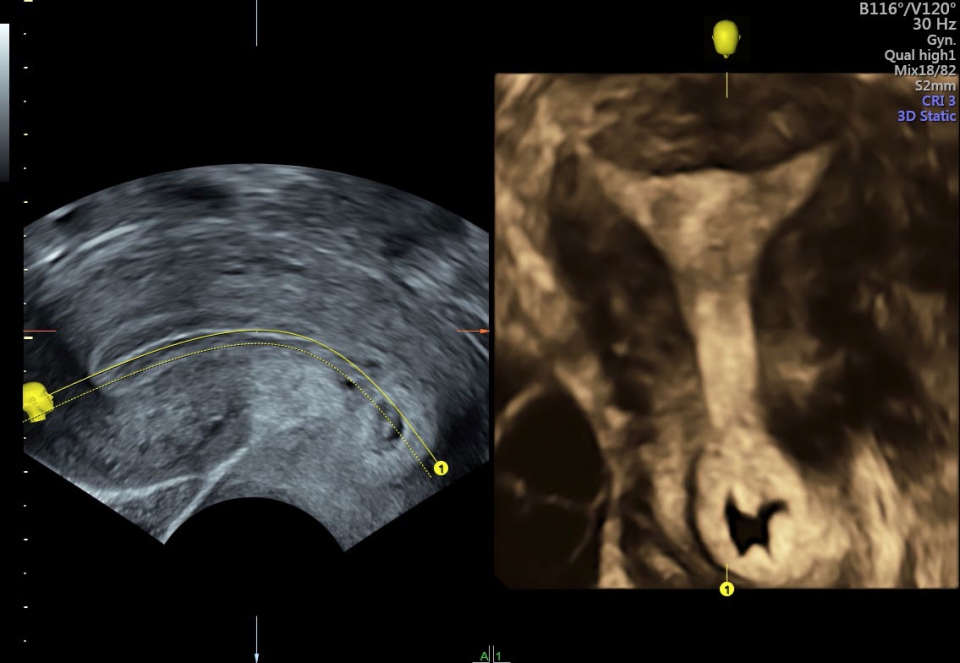

Ультразвуковой аппарат Voluson S10 оснащен чувствительным цветовым допплером, который позволяет оценить кровоток и анатомию сосудов, обеспечивая полную информацию о состоянии плода и околоплодной жидкости. Кроме того, на Voluson S10 установлен большой 22-дюймовый экран, который при использовании трехмерного шарнира может поворачиваться в различных плоскостях, обеспечивая удобство как для пациента, так и для врача.

• SonoNT (Оценка воротникового пространства) и SonoIT (Оценка внутричерепного пространства): Эти технологии позволяют проводить полуавтоматическую оценку толщины воротникового пространства и размеров IV желудочка головного мозга плода в I триместре беременности. Они обеспечивают более точную оценку этих параметров с минимальными усилиями.